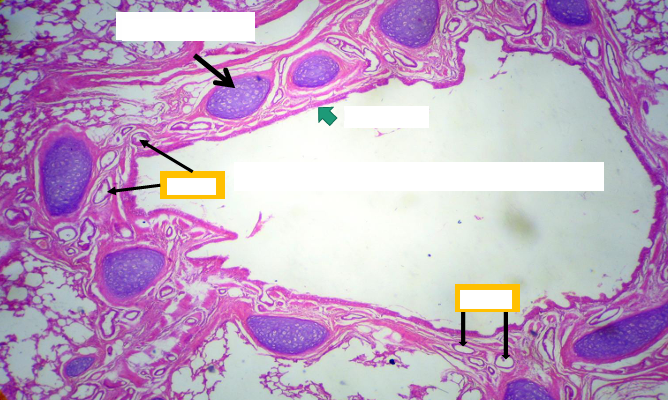

Bronchiole

Mucosa:

Epithelium: simple columnar to cuboidal partially ciliated with club cells

- Lamina propria: thin & contain elastic fibers.

Muscle layer: thin layer of circularly arranged smooth muscle.

- No goblet cells,

- No cartilage,

- No glands,

- No lymph follicles

Terminal bronchiole